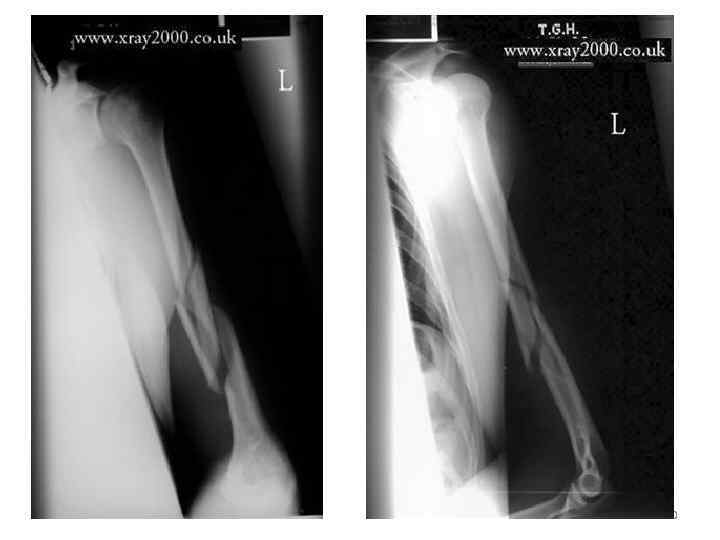

90

• На рентгенограммах левой плечевой кости в задней и боковой атипичной проекциях определяется: оскольчатый спиральный перелом средней трети диафиза плечевой кости со смещением отломков по ширине на ½ диаметра кости кнаружи и под углом 10 -15 гр. , открытым кзади. • (Клин от кручения) 91